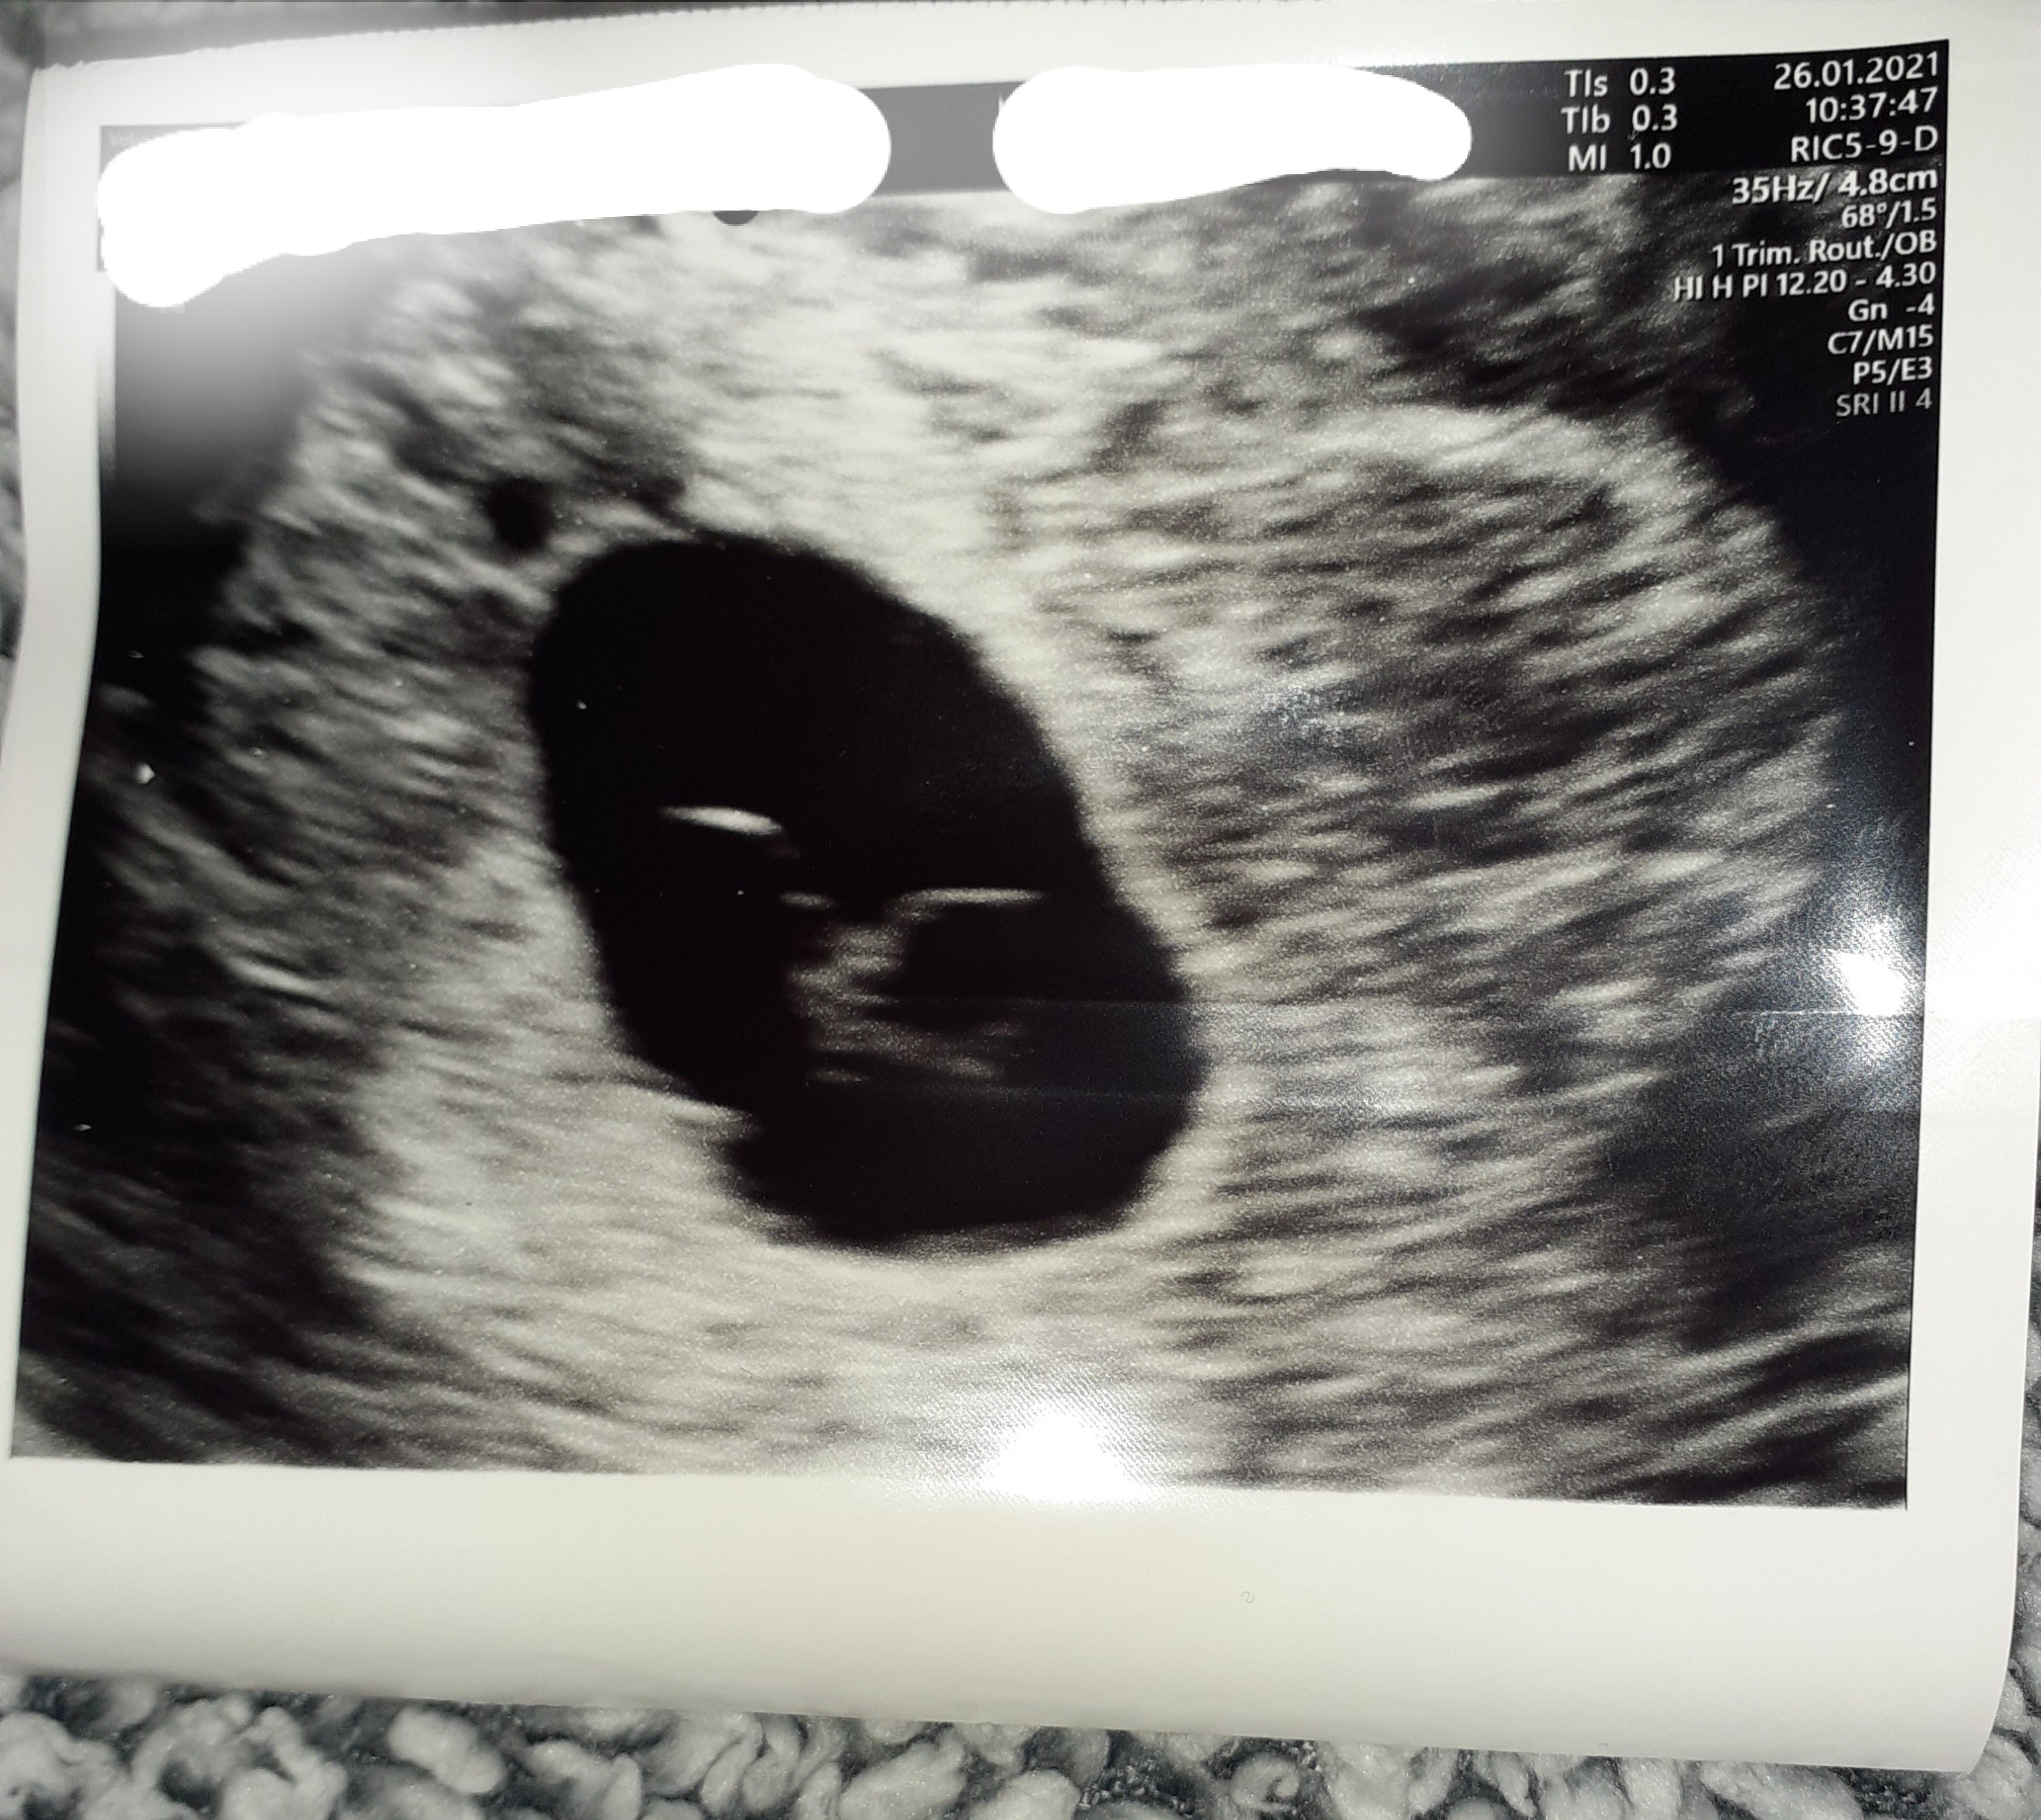

Według moich niezbyt dokładnych obliczeń powinnam być w 8tc. Byłam na usg 2 dni temu (mieszkam za granicą i tutaj ludzkie ciąże traktuje się jak ciąże na farmie dla zwierząt :-(

Położna zrobiła usg, stwierdziła że nie ma akcji serca, że płód według niej obumarł około 6 tygodnie bo jest zbyt mały na 8tc.

Zarodek ma 4.2mm i według położnej jest martwy bo nie ma akcji serca.

W niektórych krajach za granicą można wykonać badanie beta HCG prywatnie, lub jeśli nie ma pewności czy dziecko żyje czy nie poczekać jeszcze tydzień i wtedy powtórzyć USG. Niestety bez badań nic powiedzieć się nie da. Na obrazie USG pusto nie jest, czasem nawet doplera się włącza by sprawdzić czy jest obieg krwi. U takiego maleństwa każdy dzień jest siedmiomilowym krokiem. Jednak najczęściej 8tc to graniczny czas, nawet dla późnej owulacji. Tylko przy nieregularnych cyklach nigdy nie wiadomo, kiedy nastąpiła owulacja, dlatego beta daje szerszy obraz dotyczący ciąży, oczywiście w powiązaniu z obrazem USG. Wydaje się, że położna nawet rozsądnie podeszła do tematu. Kazała przyjść za kilka dni. Może zrobi jeszcze raz USG by sprawdzić zanim poda prostaglandyny?